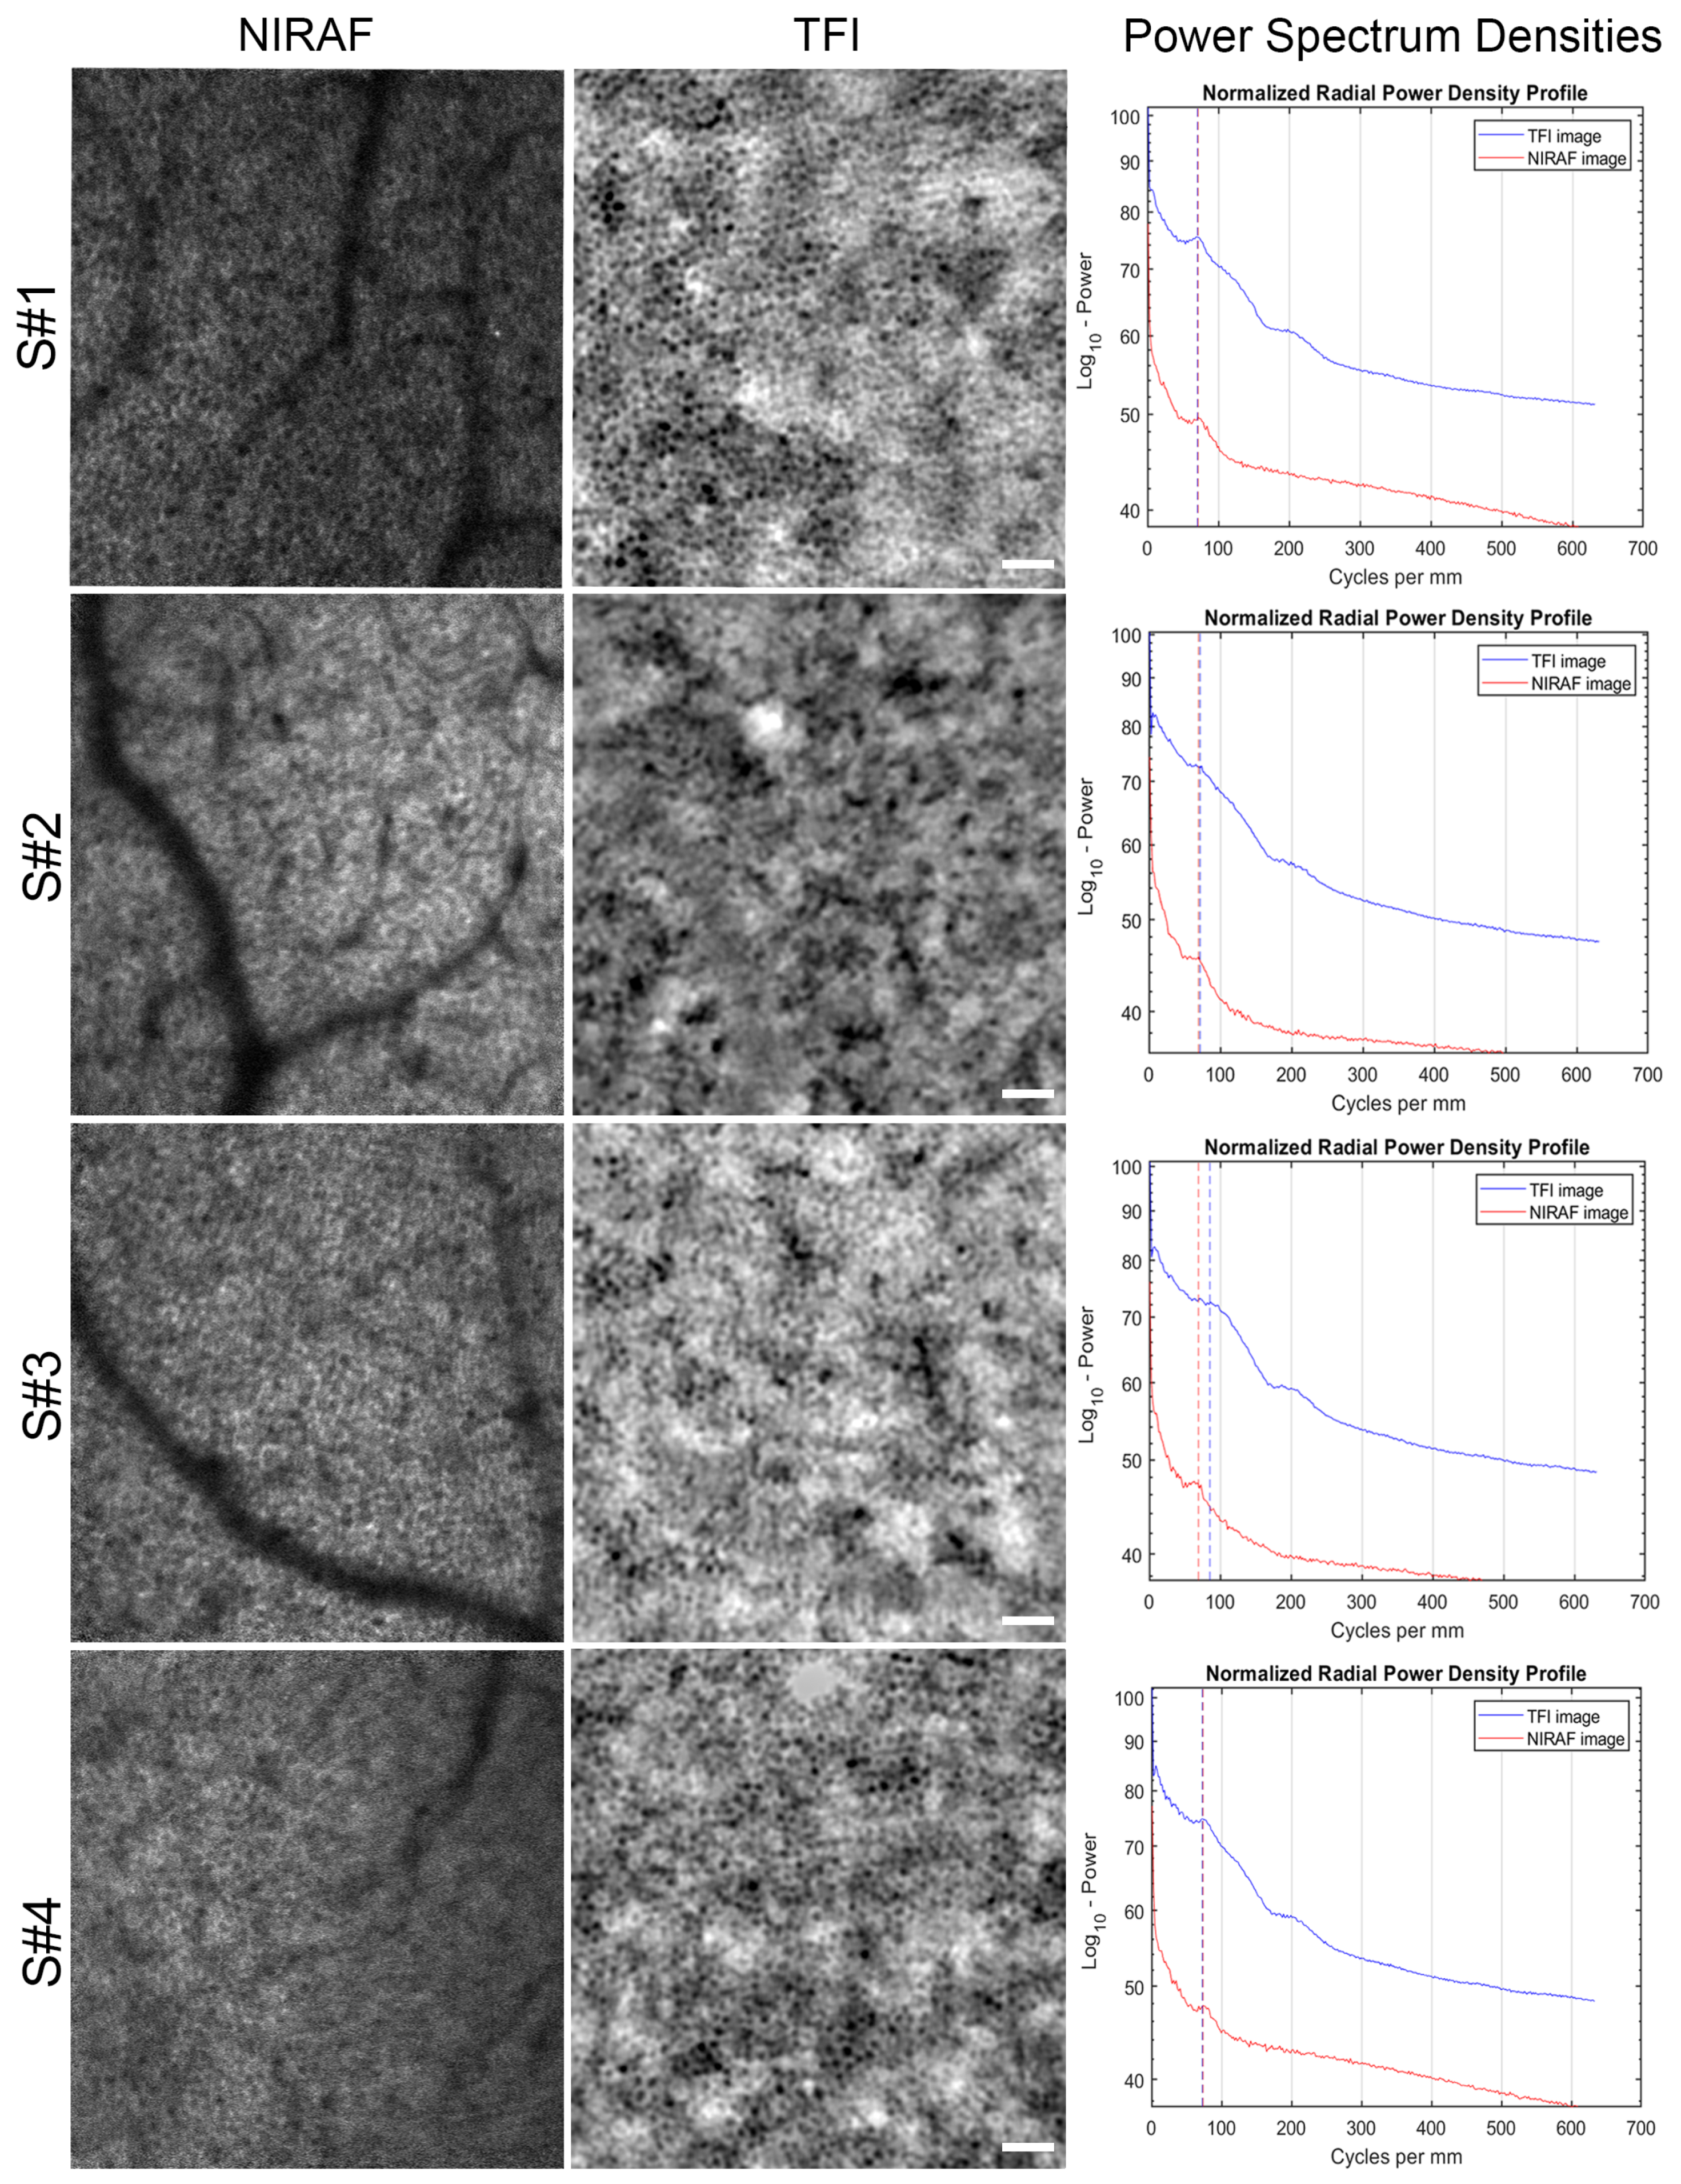

3. Results

3.1. Images of TFI and NIRAF of Same Regions

4.1. Origin of RPE Cell Contrast

4.2. RPE In Vivo Signal Variation with Eccentricity